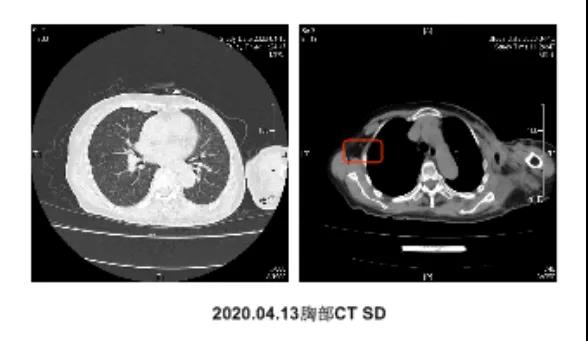

●鉴于患者已行6周期化疗,年龄较大,ER/PR强阳性等临床特征,于2019-06-19至07-23采用“来曲唑2.5mgQd+氟维司群500mg”方案的内分泌治疗,3个周期后,CT疗效评估:缩小,SD。

●同年8月出现胸壁红肿伴左上肢肿胀加重,于2019-08-27至2020-03-10行原方案的内分泌治疗联合小分子抗肿瘤血管生成剂“阿帕替尼”,共计治疗6个周期。2周期、4周期治疗后CT疗效评估均为SD。血CA153维持正常水平。6周期后查体发现,胸壁结节较前增多增大,红肿明显,CT疗效评估SD,增大。提示目前内分泌治疗方案疗效已不足以维持疾病情况不进展了。再次的血液雌二醇检测亦为绝经期水平。